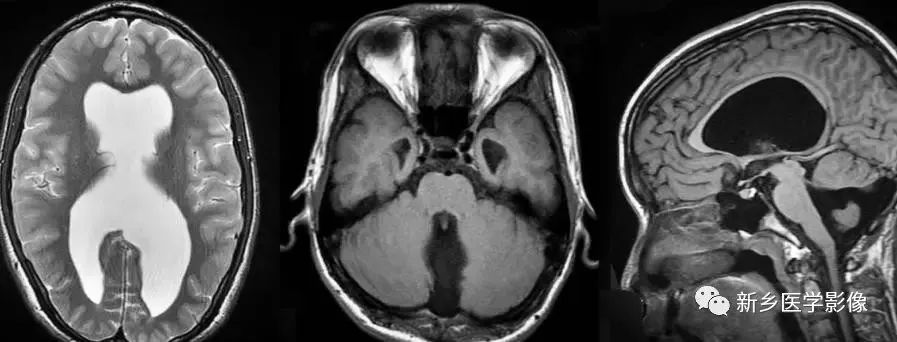

❹ Dandy-Walker’s综合症

又称第四脑室中侧孔先天性闭锁。在胚胎早期期,第四脑室正中孔及侧孔闭寒,导致四脑室呈囊性扩张,并伴有小脑蚓部及半球发育不良,扩张之四脑室向后发展,并与枕大池相连,使后颅窝扩大,小脑幕抬高。本病出现脑积水通常见于婴儿期,或者出生后即存在,但到成人期才发病。